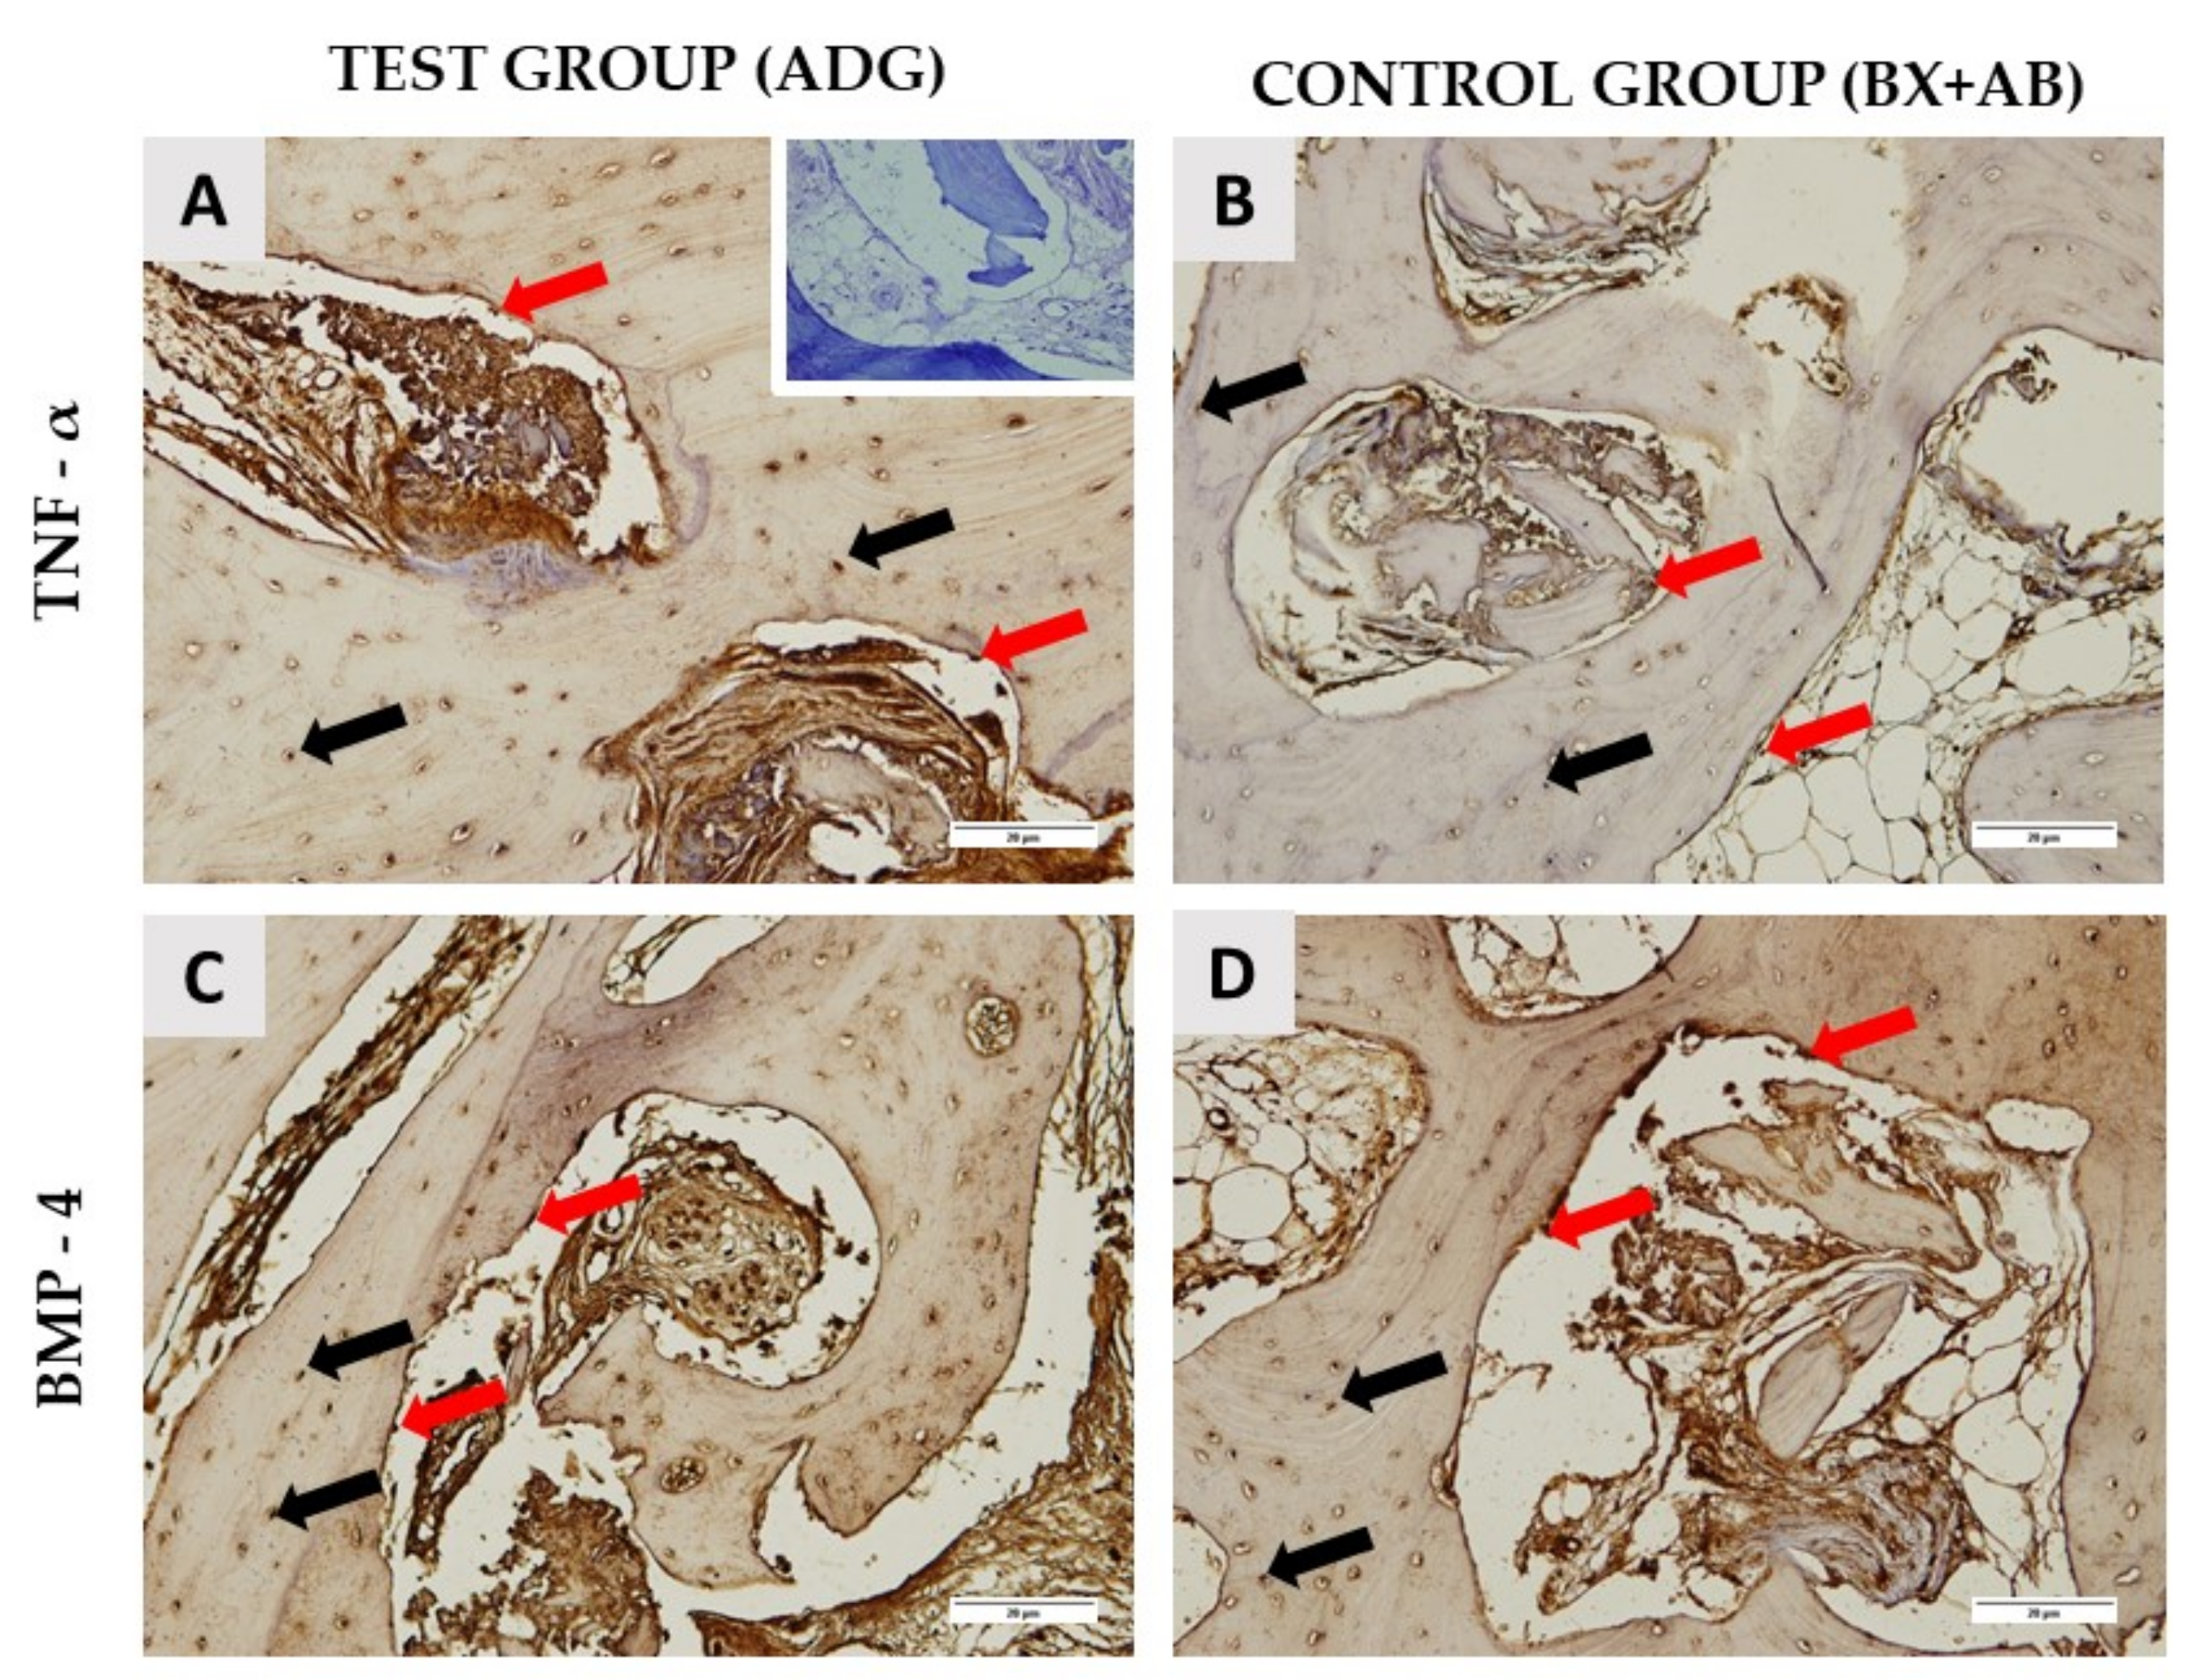

2.2. Histological Results

| TNF-α around biomaterial | 140.89 ± 4.92 | 149.96 ± 6.64 | 0.0027 |

| TNF-α new bone area | 77.49 ± 3.61 | 88.72 ± 7.1 | 0.0003 |

| BMP-4 around biomaterial | 131.26 ± 9.1 | 171.75 ± 10.5 | 0.0001 |

| BMP-4 new bone area | 108.76 ± 7.54 | 108.66 ± 8.2 | 0.9761 |